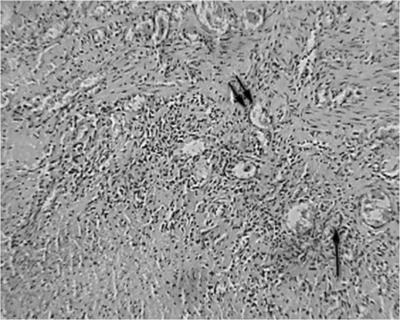

A szövettani vizsgálat a nyelőcső eltávolítása után végzett 3 esetben, a széleit a nyelőcső-mediasztinális sipoly után fibroezofagoskopii - 1 fő esetében. nyelőcső változások a stent minden esetben azonos, és képviseli a gyulladás különböző súlyosságú. A nyálkahártya talált szabálytalan hangsúlyos acanthosis, bazális réteg hiperaktivitás, dyskeratosis fejlesztésével a granulációs szövet a proximális és disztális végei a stent. A nyálkahártya alatti réteg feltárt infiltrációja limfociták, plazma sejtek és a makrofágok (ábra. 7).